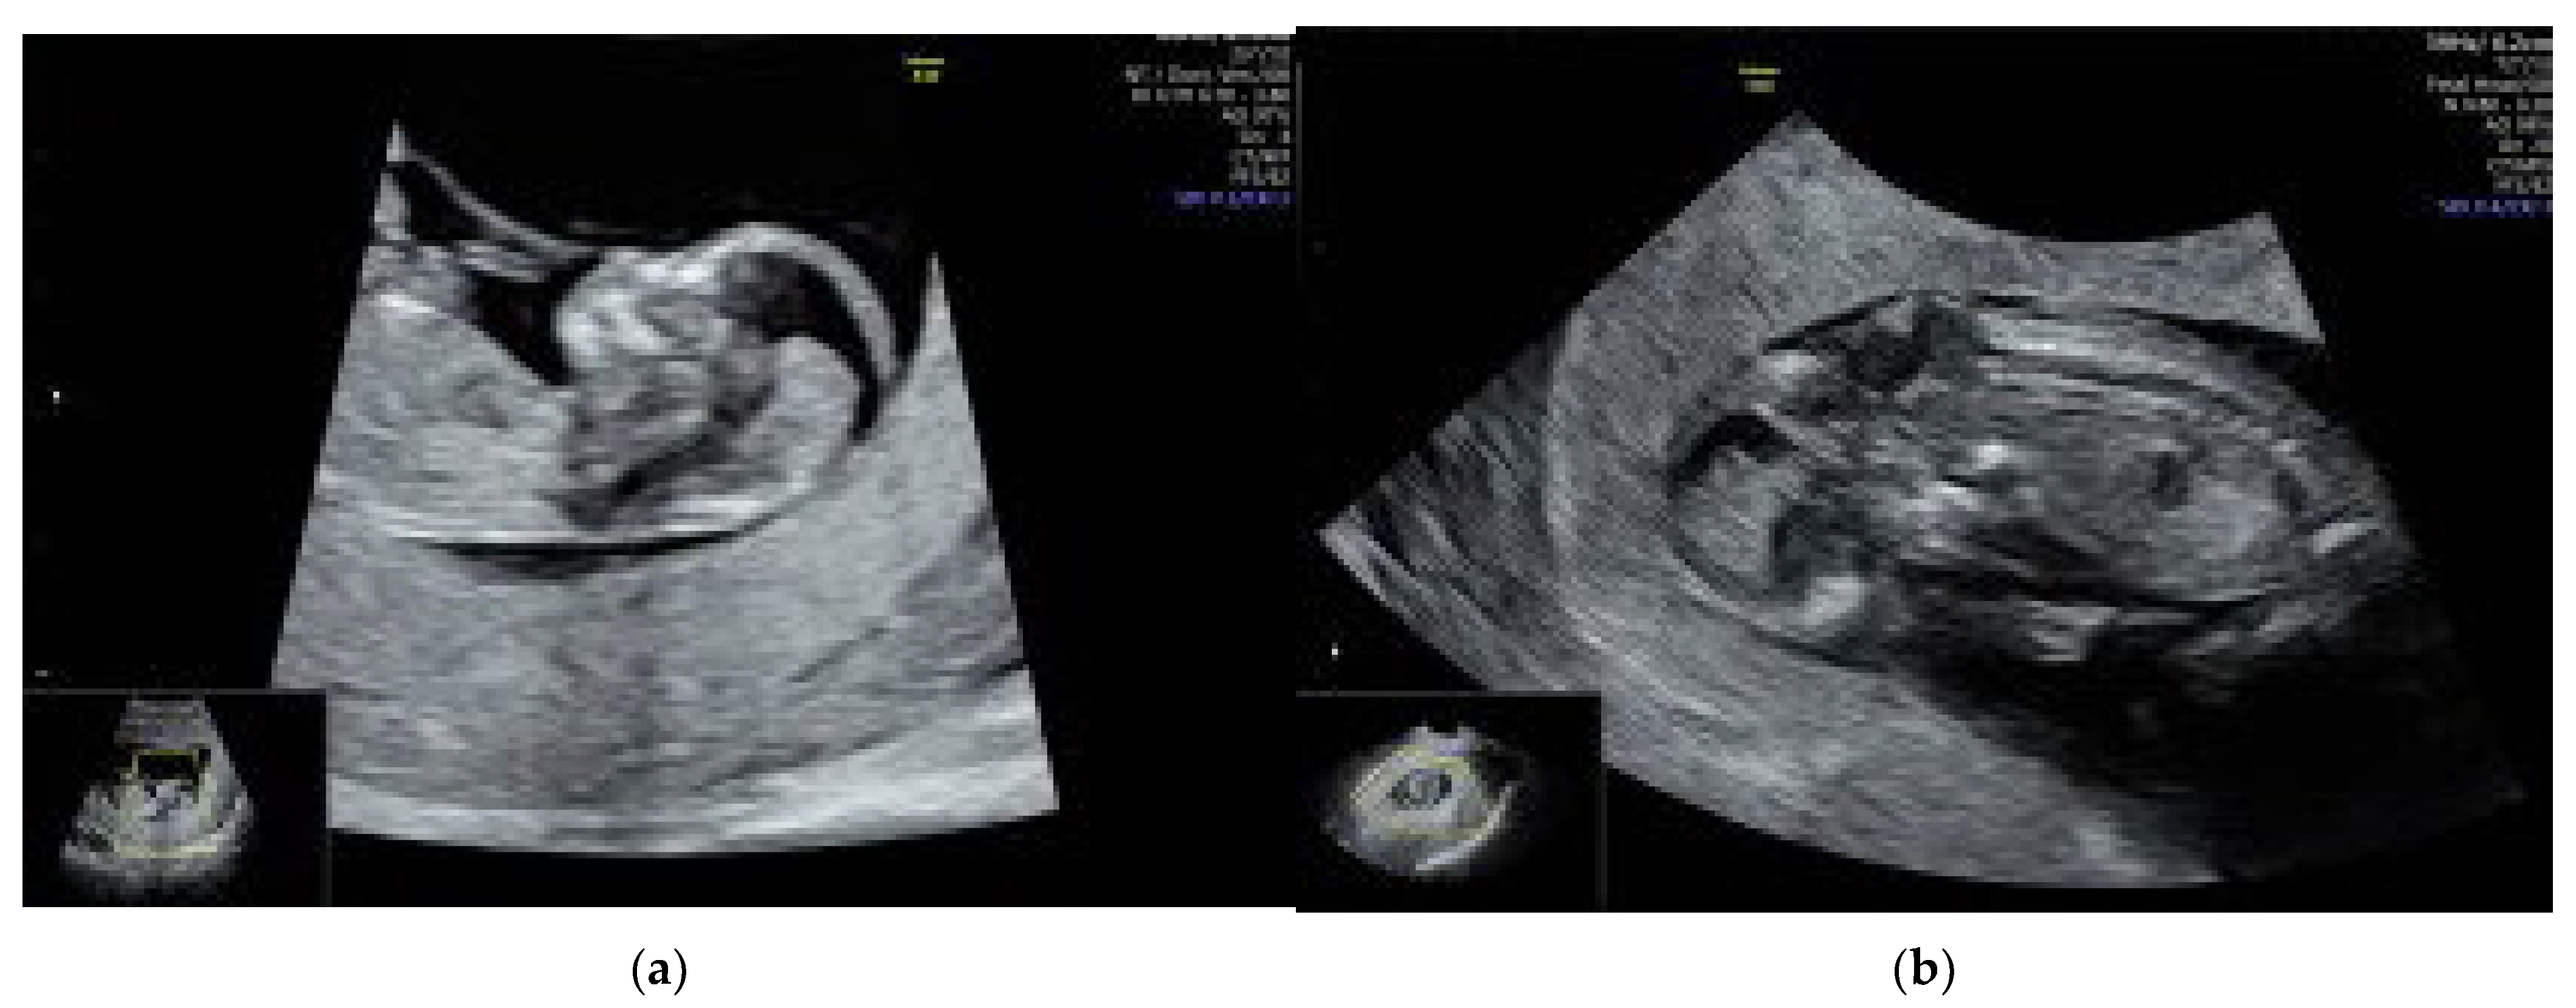

We performed a transvaginal ultrasound to better visualize the spine and the brain. On the TV scan, we could demonstrate the occipital bone defect and the herniation of the fetal brain tissue throughout it (see Figure 1b). There were no other fetal anomalies detected on a thorough ultrasound examination.

Figure 1.

On ultrasound examination, we found a fetus with a CRL of 56.1 mm corresponding to 12 weeks and 1 day, a nuchal translucency of 1.4 mm and an abnormal posterior fossa of the fetal brain. In mid-sagital view of the fetus, we could not demonstrate a normal brainstem to brainstem-occipital bone ratio. The intracranial translucency was not visible. (a) Mid-sagital view of the fetal profile; the amniotic membrane was wrapping the fetus, and the retroamniotic space was largely increased. (b) Transvaginal (TV) ultrasound scan demonstrating the occipital bone defect and the herniation of the fetal brain tissue throughout it.